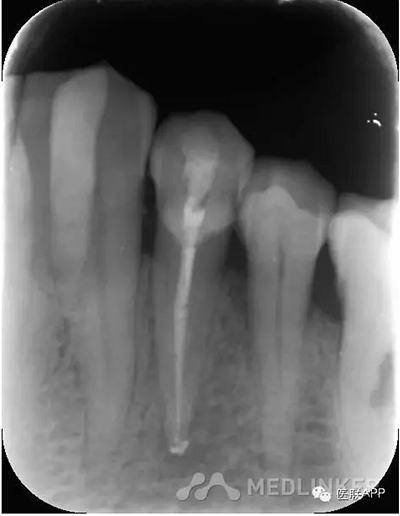

復(fù)診:去暫封,超聲蕩洗,干燥,試尖可,糊劑+熱牙膠根充,玻璃離子暫封,3月后復(fù)診,囑勿用患牙咬硬物。